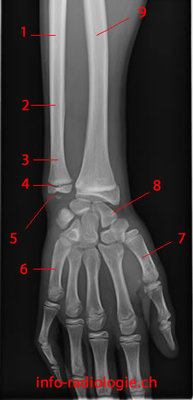

Une petite question. Dans la ronéo on nous dit que " la tete de l'ulna est situé 2mm plus haut que l'extrémité infériure du radius "

Je voulais savoir s'il s'agissait réellement de la tete de l'ulna comme dit ici, ou bien l'extrémité inférieur de l'ulna (processus styloide ulnaire) qui est situé à 2 mm plus haut que l'extrémité inf du radius ?

On parle bien de la tête de l'ulna (qui est à l'extrémité inf de l'ulna)

Mais le processus styloide de l'ulna n'est-il pas plus bas que la tete meme de l'ulna ?

Oui autant pour moi tu as complètement raison j'ai eu un petit moment d'égarement c'est bien la styloide encore désoléééééé :)